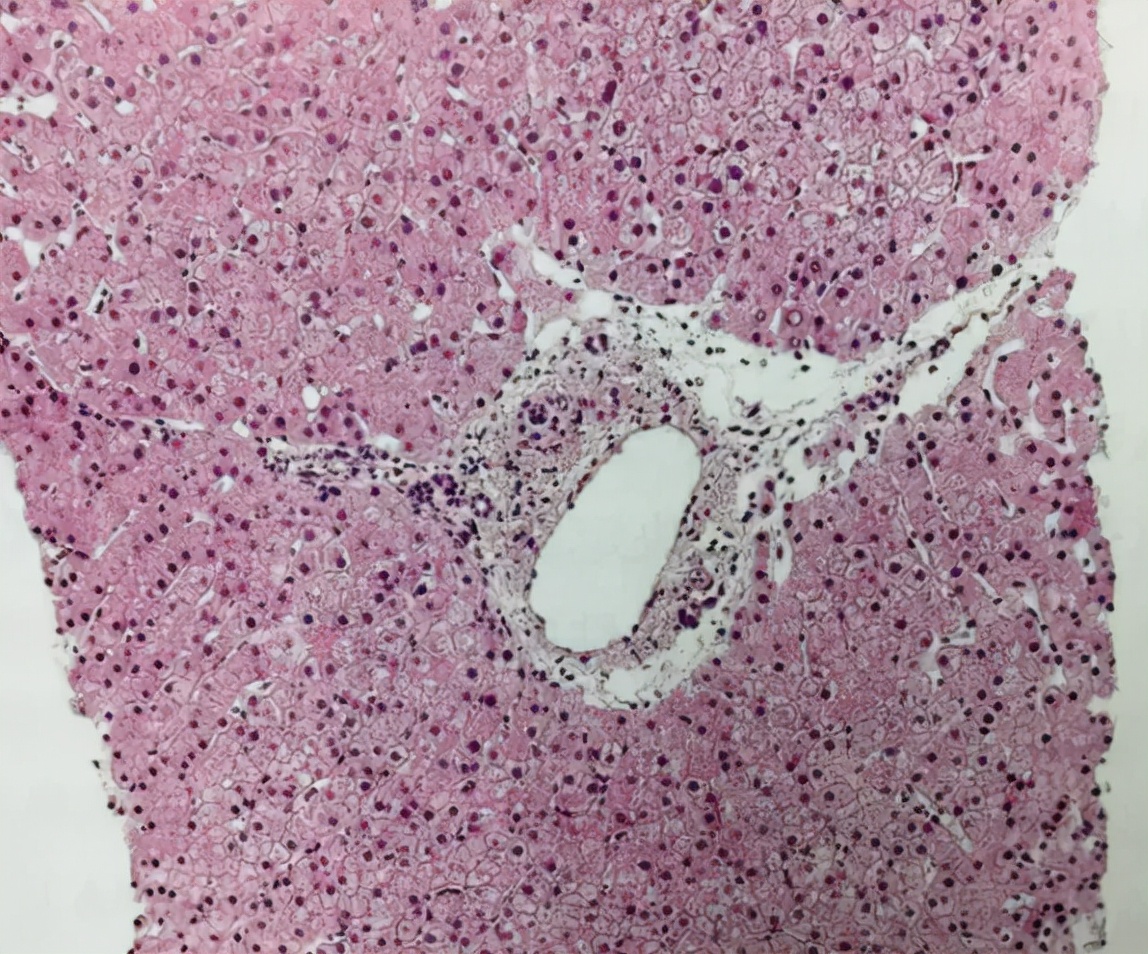

重要的是,成功治疗AIH不仅可以预防疾病进展并降低死亡率,还可以在某些情况下减轻纤维化和肝硬化(见图1)[11]。

图1. 免疫性肝炎患者经过3年免疫抑制治疗后获得了临床缓解,肝穿刺提示肝组织活检未见异常。